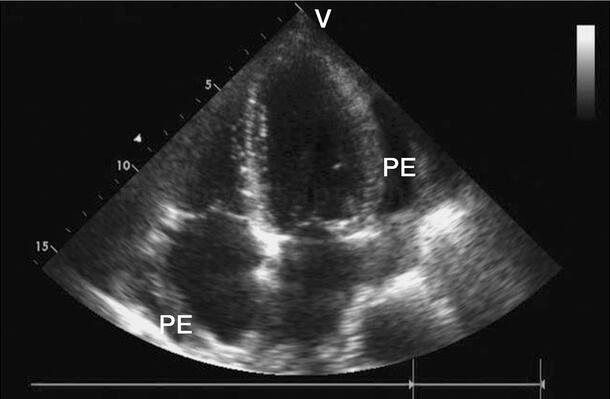

(1)M型超声心动图:心尖及心室波群切面上,左心室后壁心包腔内液性暗区宽0.5~1.0cm,见图2‐1‐223,右心室前壁心包腔内液性暗区宽约0.2~0.5cm;主动脉根部运动幅度减低,左心房后心包腔内偶见少量液性暗区。

图2‐1‐223 M型超声心动图显示中量心包积液,积液位于左室后壁PE:心包积液